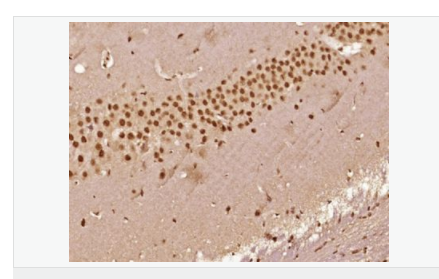

交叉反應(yīng):Human,Mouse,Rat(predicted:Dog,Pig,Cow,Horse,Rabbit,Sheep) 推薦應(yīng)用:IHC-P,IHC-F,ICC,IF

交叉反應(yīng):Human,Mouse,Rat(predicted:Dog,Pig,Cow,Horse,Rabbit,Sheep) 推薦應(yīng)用:IHC-P,IHC-F,ICC,IF

| 產(chǎn)品應(yīng)用 | IHC-P=1:100-500 IHC-F=1:100-500 ICC=1:100-500 IF=1:100-500 (石蠟切片需做抗原修復(fù)) not yet tested in other applications. optimal dilutions/concentrations should be determined by the end user. |

| 細(xì)胞定位 | 細(xì)胞核 細(xì)胞漿 |